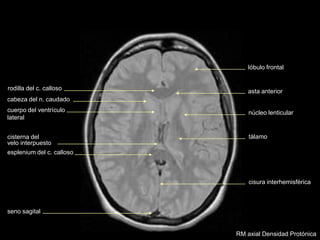

RM axial T2

asta anterior

cuerpo del ventrículo

lateral

rodilla del c. calloso

cabeza del n. caudado

cisterna del

velo interpuesto

esplenium del c. calloso

núcleo lenticular

tálamo

cisura interhemisférica

seno sagital

lóbulo frontal

RM axial Densidad Protónica